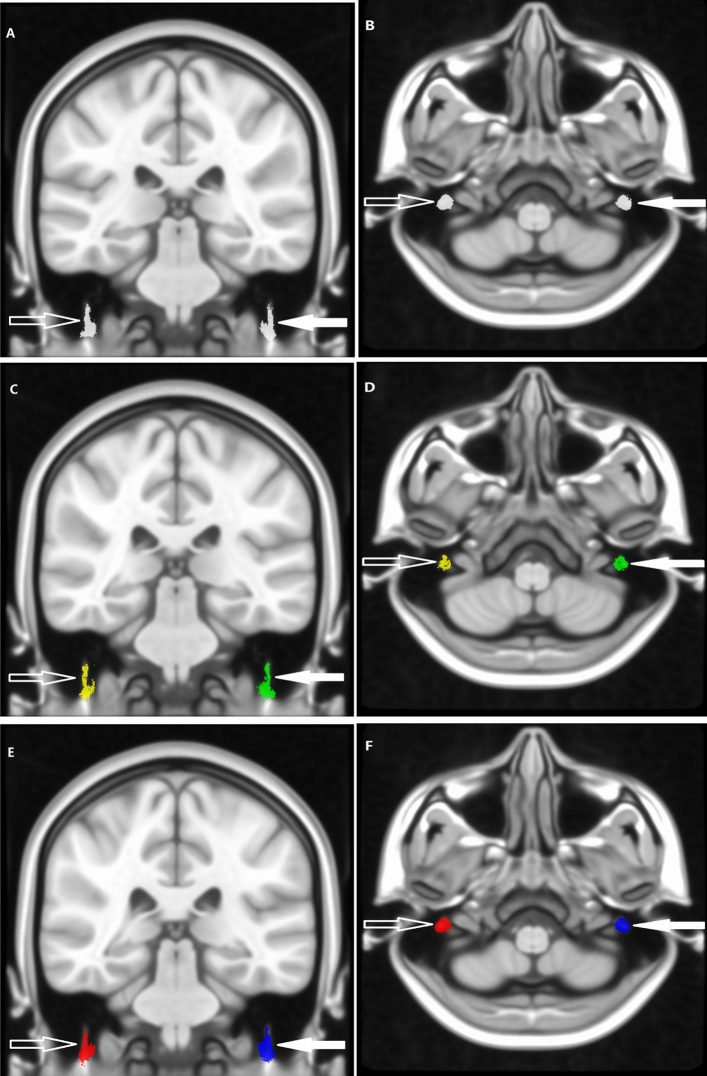

Figure 2.

The symmetrically spherical ROIs (right: red and blue; left: yellow and green) with the same diameter of 5 mm, were set on intratemporal facial nerves (right: hollow arrow; left: solid arrow) in the 0.4 mm3 voxel MNI common space (named MNI152_T1_0.4 mm).

After eddy, current correction of the DTI data, affine transformation, and nonlinear matching were performed on the diffusion images matching with the MNI152_T1_0.4 mm template without skull-stripping by using the FSL (Oxford, UK). Then the voxel size of the DTI was resampled to 0.4 mm3 in the common space of the MNI152_T1_0.4 mm template. DTI data were used to track each intratemporal facial nerve fiber in 0.4 mm3 common space by using TrackVis and its Diffusion Toolkit (DTK). The intratemporal facial nerve fibers were traced with a threshold value of FA > 0.15 and an angle threshold value of 60°. To reduce errors, the step length of fibers less than 2 mm was discarded (Fig. 3).

Figure 3.

DTI fiber tracing of bilateral intratemporal facial nerves was performed. A patient (A, B) is a female, 46 years old, with right facial paralysis for 3 days and H-B facial nerve function grade IV. A patient (C, D) is a male, 23 years old, with right facial paralysis for 7 days and H-B facial nerve function grade III. A patient (E, F) is a male, 59 years old, with left facial paralysis for 1 day and H-B facial nerve function grade III. The left (solid arrow) and right (hollow arrow) intratemporal facial nerves were indicated by the arrows respectively.

All results then were used to construct the maximum probability map (MPM), which assigned the most probable labels to each voxel according to the majority rule across subjects (Fig. 4). The indexes of DTI, named fractional anisotropy (FA), mean diffusivity (MD), axial diffusivity (AD), and radial diffusivity (RD), were calculated and extracted based on MPM.

Figure 4.

According to the majority rule across subjects, the MPM of bilateral intratemporal facial nerves was constructed. The MPM of the healthy people (a, b), the patients (c, d), all people including the healthy people and patients (e, f). The left (solid arrow) and right (hollow arrow) intratemporal facial nerves were indicated by the arrows respectively.

In the present study, the MPM of 18 healthy people was named 18-Health-MPM, the MPM of 19 patients people was named 19-Patient-MPM, and the MPM of all 18 healthy people and 19 patients were named 37-All-MPM, respectively.